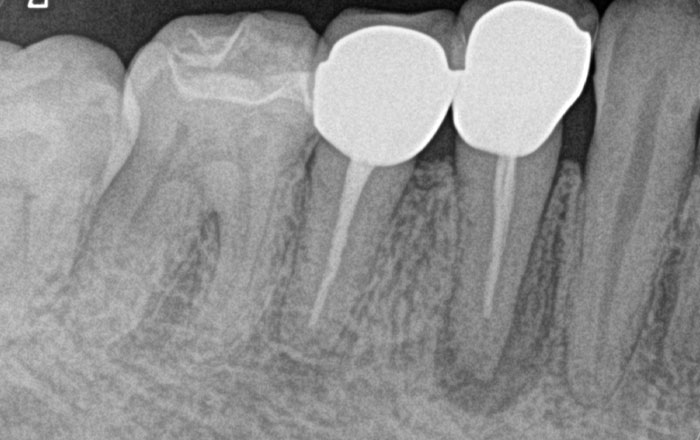

スケーリング(保険適用)

スイス・EMS社製の超音波スケーラーで、歯の表面や歯と歯茎の間にある歯垢や歯石を痛みなく取り除きます。